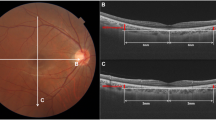

Measurement of DFD

Measurement of DFD was performed with ImageJ software (available in the public domain at http://rsbweb.nih.gov/ij/; www.nih.gov, National Institutes of Health, Bethesda, MD, USA), based on the coordinates of the fovea and the center of the optic disc. For this purpose, we used carefully registered OCT projection images, as illustrated in Fig. 3. We used the LSO fundus image with the macular color thickness map overlay to localize the fovea. The fovea was automatically detected by the OCT software. Subsequently, the enface optic disc image (RNFL thickness deviation map) from the RNFL thickness report was exported and manually registered to the LSO fundus image with Illustrator CS4 software (Adobe Systems Inc., San Jose, California). For this, the transparency of the optic disc image was set to 50% to allow visualization of the underlying LSO fundus image; the retinal vessel trajectories were used as a reference. The optic disc center and the disc margin were determined by the built-in software and shown on the RNFL thickness deviation map, based on the margin of Bruch’s membrane. The DFD was then measured by using the ImageJ software on the overlaid images43,44.

Measurement of optic disc-fovea distance (DFD) on SLO fundus image. The fovea (point F) was automatically detected by the OCT software on the SLO fundus image with the macular color thickness map. The enface optic disc image (RNFL deviation map) with the optic disc center labelled (point D) by the OCT software was manually registered to the SLO fundus image with Illustrator CS4 software using the retinal vessels as reference. Measurement of DFD (distance from F to D) was performed with ImageJ software based on the coordinates of the fovea and the center of the optic disc.